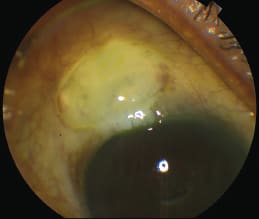

Figure 2. The second patient’s right eye showing the bleb three weeks after bleb needling. Visual acuity was 20/25, IOP 13 mm Hg, massaged down to 10 mm Hg with bleb growth. We continued prednisolone drops at six times a day for another three weeks until the next follow-up. We implanted an Ex-press shunt with 0.2 mg/ml MMC for four minutes in June 2008 after the patient responded poorly to maximal medical therapy (MMT) and SLT. IOP remained stable between 9 and 11 mm Hg for almost four years, then in April 2012 IOP was 13 mm Hg. Stepwise medical therapy was initiated. In July 2012 IOP was 21 mm Hg despite MMT, the bleb was avascular and cystic with a ring of steel around it. We scheduled bleb needling in the OR for late August 2013. Bleeding was significant but not excessive. IOP was 11 mm Hg on postoperative day one, but elevated to 14 mm Hg at one week. YAG laser to the tip lowered IOP to 7 mm Hg. (Figure 2). |